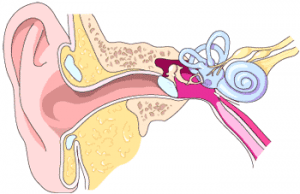

Ausies skausmas – vienas dažniausių skundų, dėl kurių pacientai kreipiasi į bendrosios praktikos gydytojus ir gydytojus otorinolaringologus. Ausies inervacija sudėtinga, todėl ausies skausmas gali atsirasti ir dėl pačios ausies patologijos (64 pav.), ir dėl kitų organų patologijos. Dėl šios priežasties kartais nelengva diagnozuoti tikslią ausies skausmo priežastį, taip pat nelengva nustatyti ausies skausmo priežastį mažiems vaikams dėl anatominių jų ausų ypatumų.